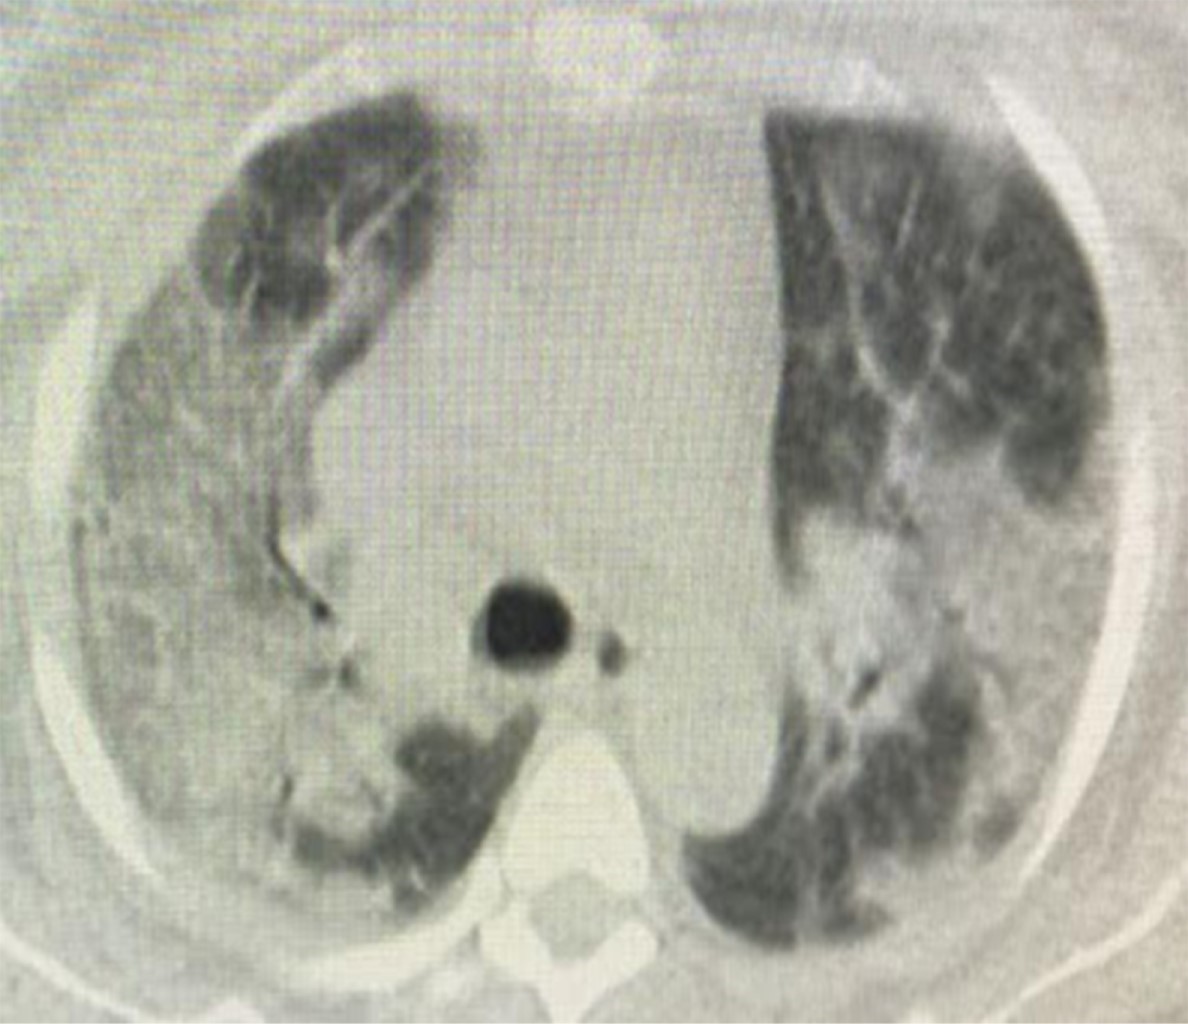

Figure 3